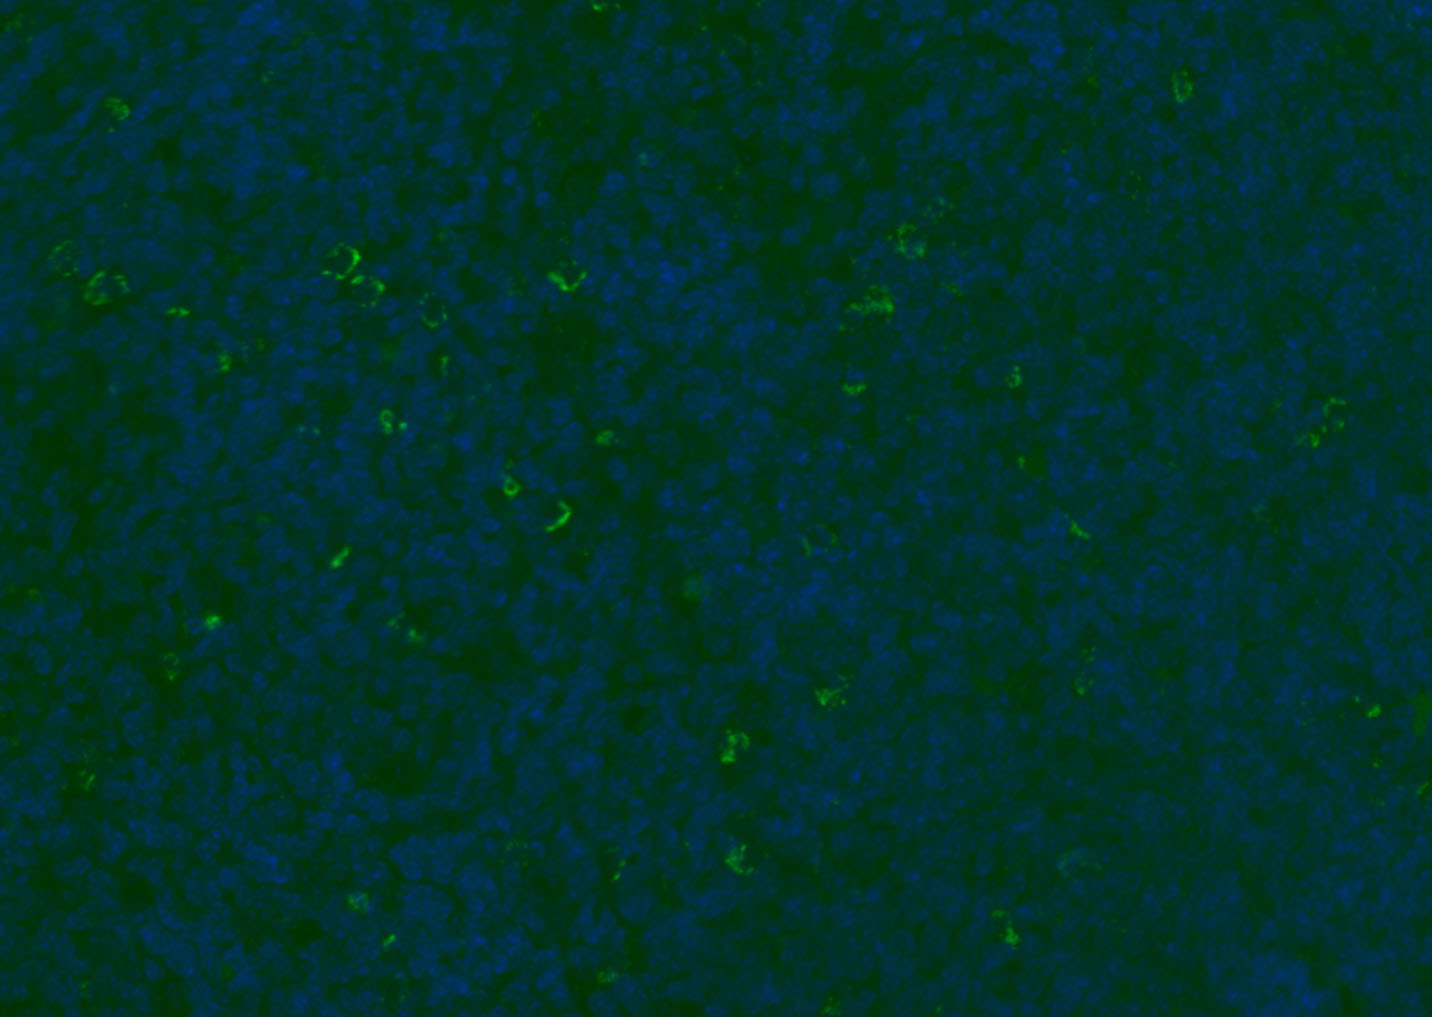

Paraformaldehyde-fixed, paraffin embedded (rat thymus); Antigen retrieval by boiling in sodium citrate buffer (pH6.0) for 15min; Blocking buffer (normal goat serum) at 37°C for 30min; Antibody incubation with (CD8B) Polyclonal Antibody, Unconjugated (bs-4914R) at 1:200 overnight at 4°C, followed by a conjugated Goat Anti-Rabbit IgG antibody (bs-0295G-FITC) for 90 minutes, and DAPI for nuclei staining.